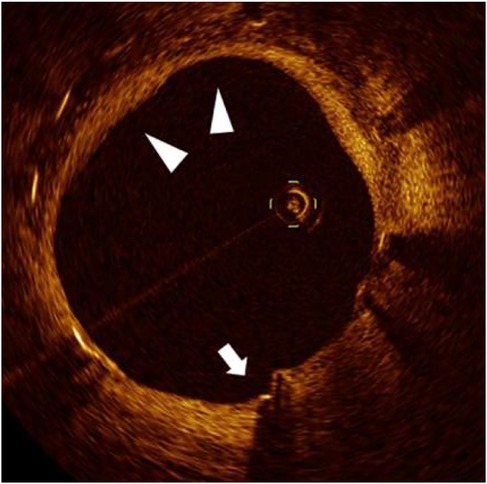

Background: Biological aging and prolonged cold exposure each impair vascular healing after implantation of a drug-eluting stent. However, their combined effect—particularly in older adults living in cold climates—remains poorly understood. Objective: To evaluate the joint impact of aging and cold exposure on vascular healing and their association with major adverse cardiovascular events (MACEs) after sirolimus-eluting stent implantation. Methods: In this retrospective cohort study, 119 patients were stratified into three age groups (≤55, 56–65, and >65 years). Vascular healing was assessed using serial optical coherence tomography (OCT) at 6 and 12 months, with a focus on strut coverage, neointimal hyperplasia (NIH), and spatial heterogeneity. Cold exposure was quantified with the validated Cold Exposure Diary Questionnaire and corroborated by regional meteorological data. The primary end point was the incidence of MACEs at 12 months. Results: OCT showed delayed endothelialization at 6 months in patients above 65 years compared to younger cohorts (uncovered struts, 11.7% vs. 6.1%; P < 0.001), along with accelerated late-phase NIH progression (3.33 vs. 1.67 μm/month; P < 0.001). Prolonged cold exposure (>12 h/day) was independently associated with greater neointimal heterogeneity (P=0.003) and a higher risk of MACEs (hazard ratio, 3.42; 95% CI, 1.65–7.11). A 4D Risk Score, combining OCT-derived healing metrics and cold-exposure data, predicted MACEs; however, external validation is required. Conclusions: In older patients, the interaction between aging and prolonged cold exposure results in biphasic vascular healing, characterized by early delayed endothelialization followed by excessive neointimal proliferation. The proposed 4-D Risk Score may facilitate individualized risk stratification after percutaneous coronary intervention and warrants prospective validation.